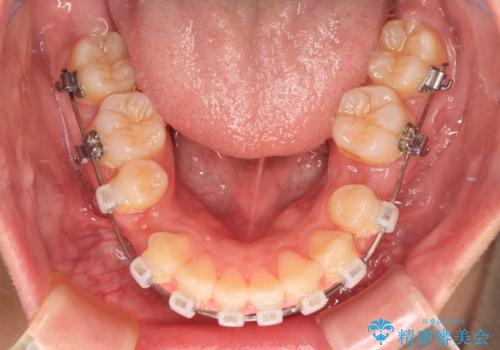

- 矯正装置

- クリアブラケット

くちばしのように前歯が突出していたため、口元を積極的に引っ込めるために、上下左右の小臼歯4本を抜歯することとしました。

また、上顎歯列が下顎に対して前方位に位置していたため、補助装置を用いて上顎歯列を後方に移動させ、より積極的に口元を下げるようにしました。